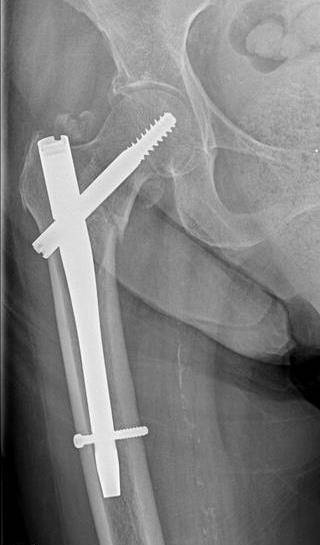

Блокируемый интрамедуллярный синтез (БИОС) применяется при диафизарных переломах (переломы трубчатых костей в средней части). Названием методики связано с тем, что металлический стержень-фиксатор блокируется в медуллярном канале винтовыми элементами.

Остеосинтез шейки бедренной кости без осколочных смещений проводят закрытым способом. Для повышения стабилизации скелетной системы фиксирующий элемент вводится в тазобедренный сустав с последующим закреплением в стенке вертлужной впадины.

После выбора пластины необходимо подобрать винты. Как и металлоконструкции, их изготавливают из титана. И в зависимости от повреждения требуется определенный винт. Например, компрессирующие винты используются при поперечном диафизарном переломе предплечья для стягивания отломков, а блокирующий применяют при операции в тазобедренного сустава, потому как он обеспечивает надежную фиксацию и угловую стабильность

Внутрикостными (интрамедуллярными) стержнями с блокированием винтами или, как еще их называют, штифтами выполняют фиксацию переломов трубчатых костей, а в частности поперечных и винтообразных переломов с небольшим количеством отломков и осколков. Также предпочтение для внутрикостного остеосинтеза отдают ввиду скорости операции, миниинвазивности и малой травматичности операции. Стоит сказать, что фиксация стержнями очень хорошая и дозированную нагрузку на оперированную конечность разрешают давать уже через нечколько дней.

После успешной операции и сращения перелома, как правило, удаляют динамический винт и увеличивают нагрузку на конечность, для полного сращения перелома. Через 1 год после операции, когда перелом полностью сросся, в плановом порядке выполняется удаление винтов и стержня.